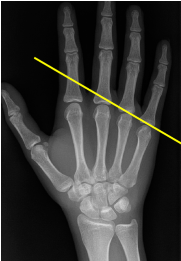

Q what is the name of this measurement? and what is the average + range?

A: Metacarpal Sign

assesses the alignment of the metacarpal heads. No average or range is specified.